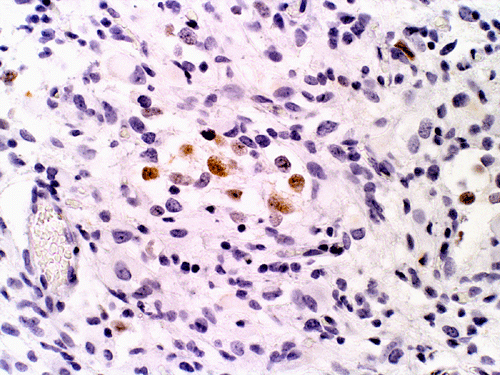

At low magnification, the lesion appears as a spindly, desmoplastic neoplasm with storiform arrangement that could be seen in some mesenchymal tumors (Panel A). On higher magnification, the overall pleomorphism is relatively mild. Mitotic figures are not readily seen. There are some round to triangular cells that are surrounded by a rim of retraction artifactual space from the surrounding desmoplastic component  (Ţ in Panel B). These cells seem like a drop of oil floating on water. The morphologic features of these cells are suggestive of ganglionic cells and/or gemistocytic astrocytes. In other areas, tumor cells containing melanin pigment (Panel C) are present. Deposition of reticulin material can be seen essentially around every single cells (Panel D). Scattered within the tumors are large ganglionic that can be well demonstrated by immunohistochemistry for synaptophysin (Panel E). Tumor cells with mature neuronal phenotype is also immunoreactive for NeuN (Panel F). Immunohistochemistry should that the amount of astrocytic cells far out numbered ganglionic cells (Panel G). Cells that express melanin are also strongly positive for HMB45 on immunohistochemistry.

Microscopically, the desmoplastic activity is so widespread that it would suggest sarcomas to the novices. Recognition of this potential pitfall is of importance during intraoperative consultations. DIA and DIG have known tendency to extend into the Vichow-Robin space. However, there is a typical, marked demarcation between the desmoplastic tumor and the cortex. Spindle cells arranged in fascicles, storiform, or wholed pattern intermixed with collagenous component are common findings and is particularly associated in areas with leptomeningeal involvement. On detailed examination, neoplastic  neuroepithelial cells with features of astrocytes, gemistocytic astrocytes, and neurons (ganglion cells) are common. It is very common that the gemistocytic astrocytes and ganglionic cells have a retraction, artifactual space at their cytoplasmic border. These large cells appear like drops of oil in water (i.e., the desmoplastic component). The collagenous component will stain blue and the neuroepithelial component will stain pink or red on Masson’s trichrome. A reticulin stain will show deposition of reticulin material around individual tumor cells. Significant nuclear pleomorphism is not a usual feature of these tumors. Mitosis is quite uncommon and the Ki-67 labeling index for cyclinc cells ranges from less than 0.5% to 5% 2. Necrosis and endothelial proliferation should not be seen. The glial component can be well demonstrated by immunohistochemistry for GFAP. The ganglionic component can be well demonstrated by immunohistochemistry for synaptophysin, neurofilament proteins, synaptophysin, NeuN, class III beta-tubulin and MAP2.